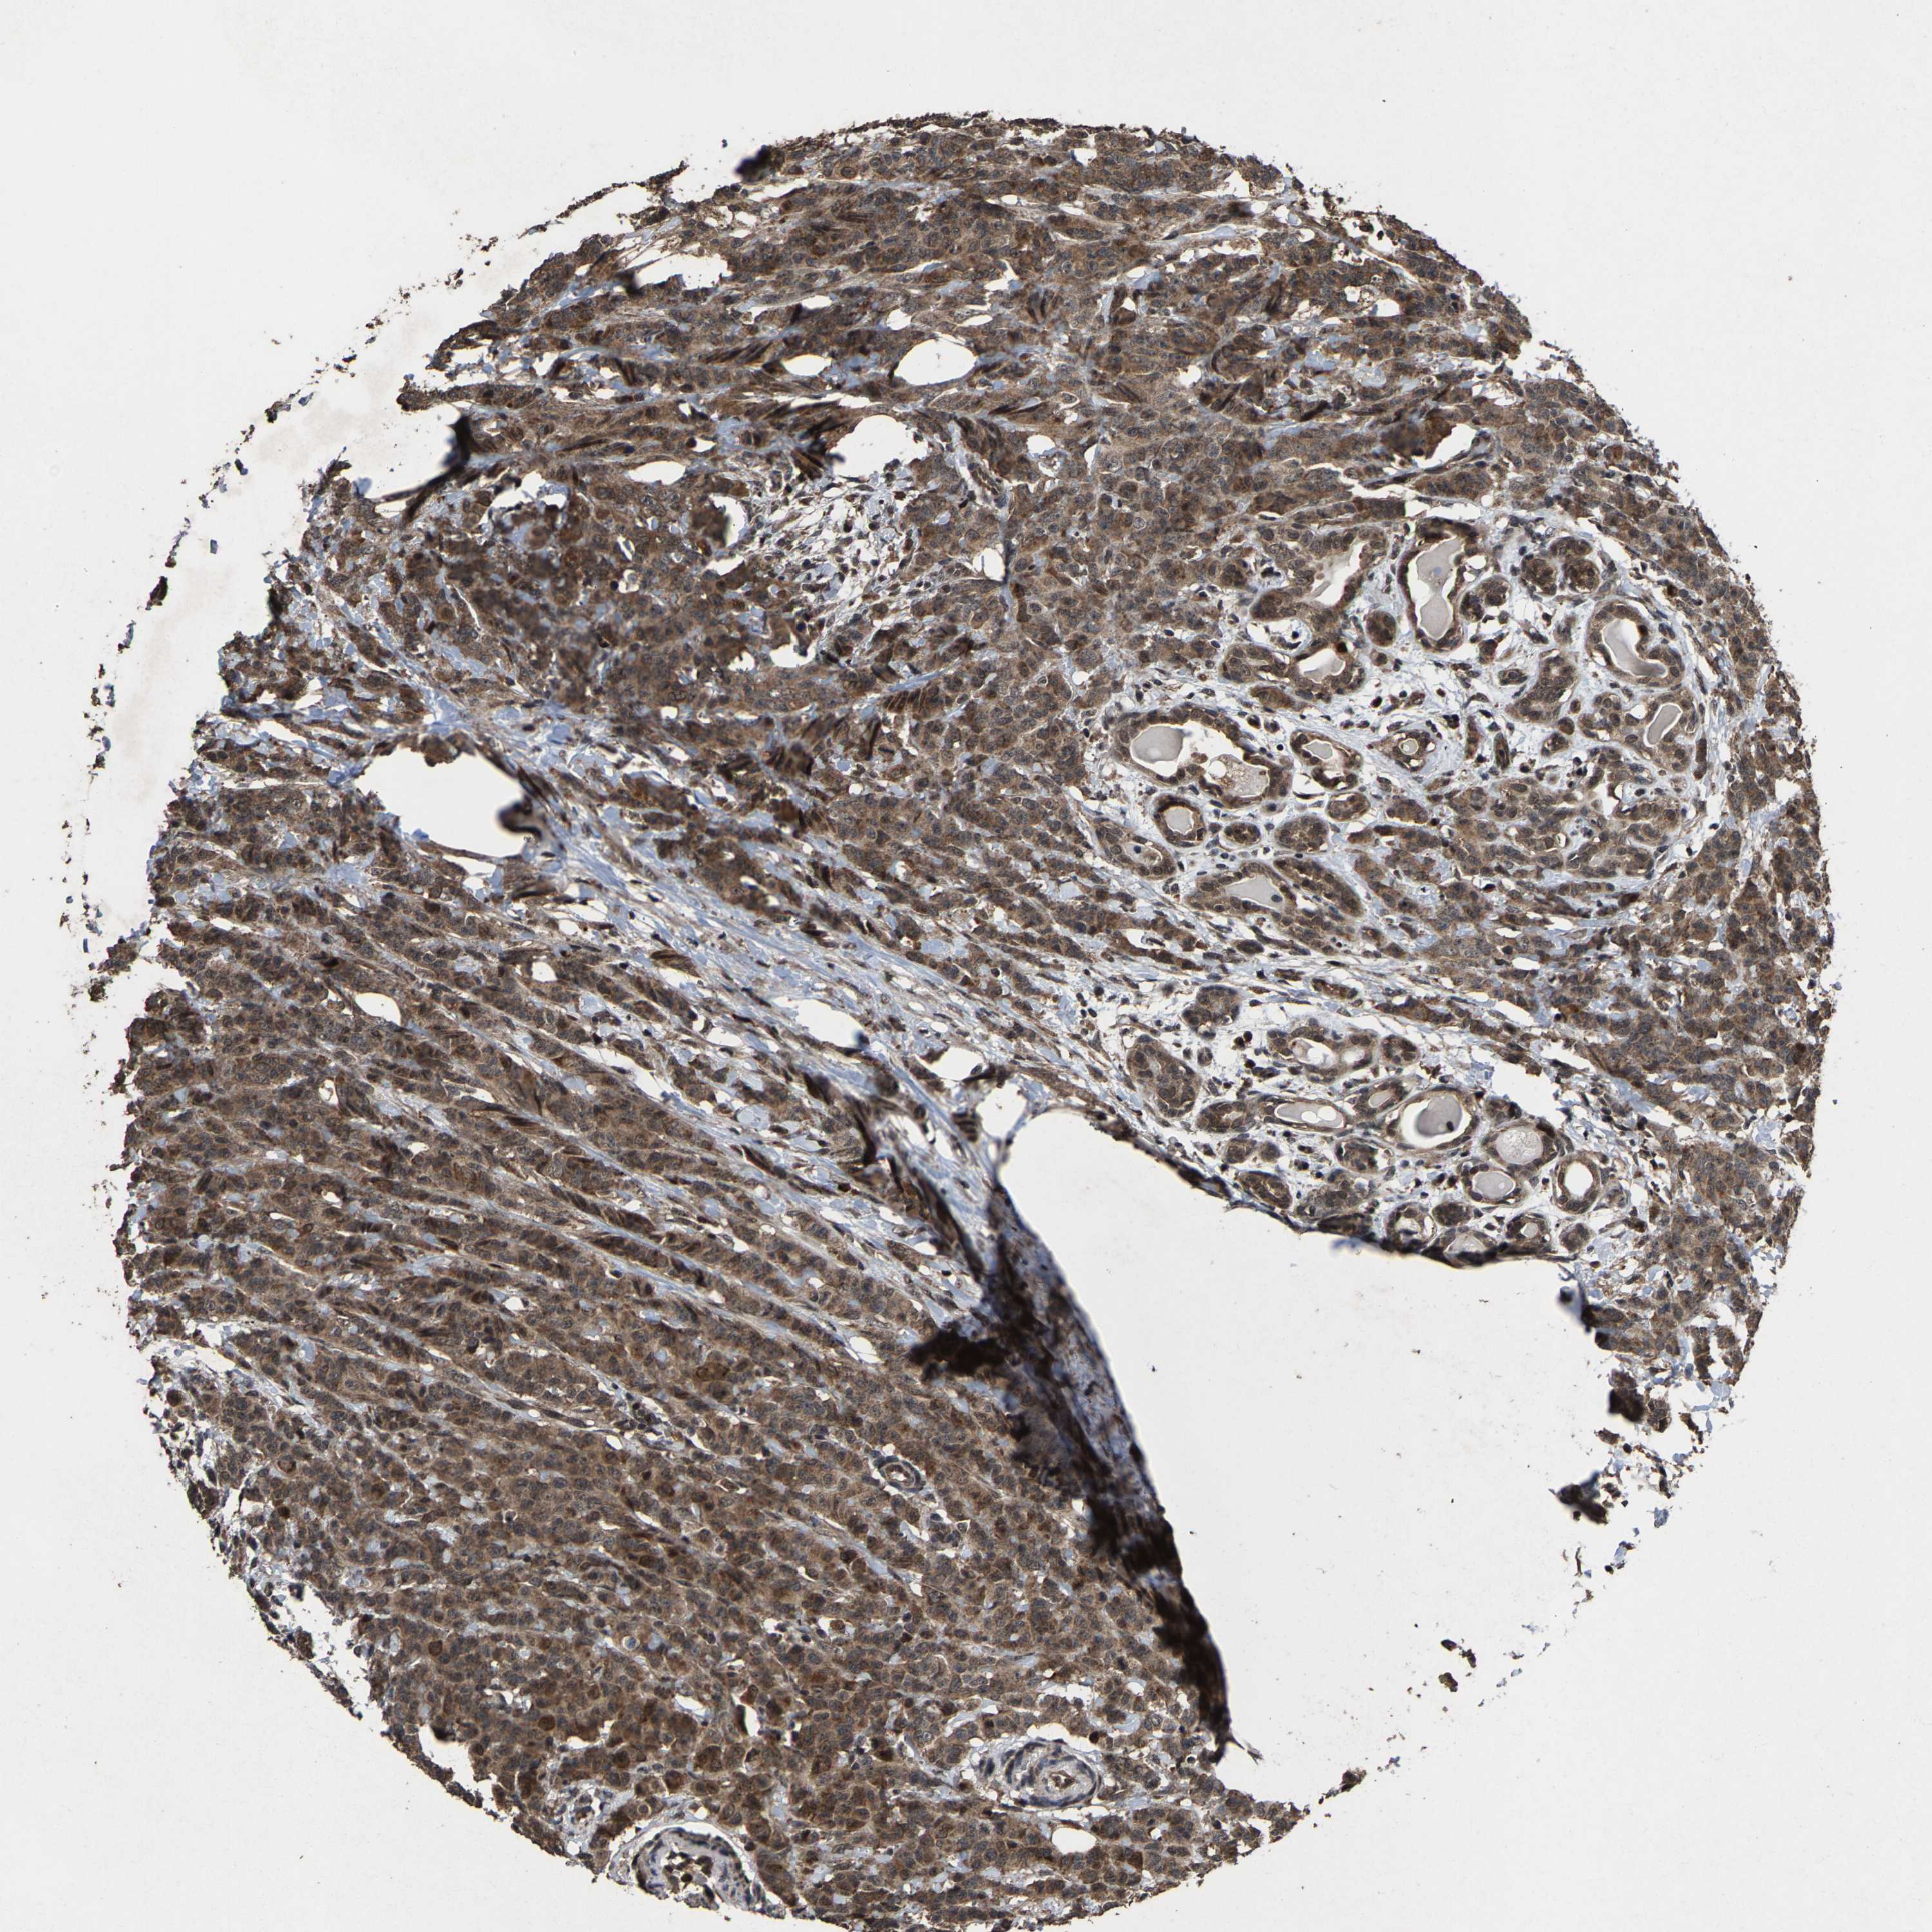

BRCA TCGA BRCA VALIDATION PROTEIN EXPRESSION